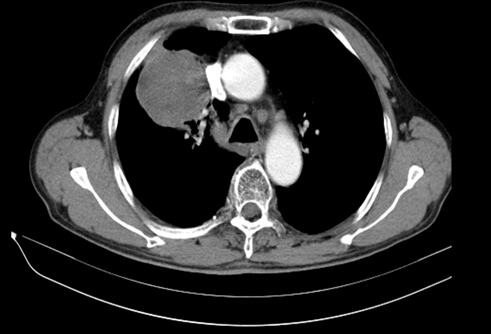

1、 氬氦刀靶區(qū)成像邊界即是消融邊界,不會(huì)產(chǎn)生偽影,可達(dá)到“所見即所得”的最佳。為臨床治療提供準(zhǔn)確影像依據(jù),可避免治療不足造成腫瘤殘留,或過度治療造成相鄰組織損傷。在CT圖像中,由于組織結(jié)冰后體積增大,靶區(qū)密度降低,冰球圖像下降40-50HU,形成清晰的陰影區(qū)。在B超成像中,冰是弱回聲的(暗區(qū)),冰球邊緣呈強(qiáng)回聲區(qū)(亮帶)。

治療前